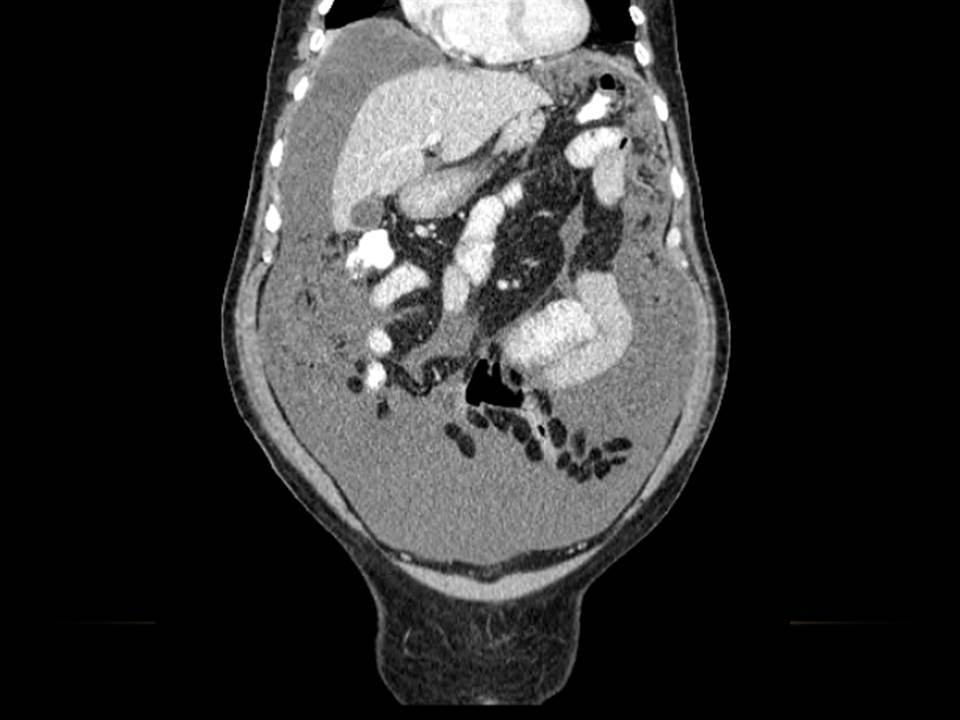

Cuadro clínico de 1 mes de evolución caracterizado por distensión abdominal e hiporexia.

Paciente de 12 años con dolor abdominal. Remitida para estudio de masa intraabdominal.